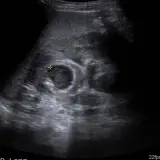

Over 2,100 interactive radiology cases, curated by radiologists for your level of training. Scroll, window, and view cases full screen — just like on PACS. Click linked findings in each writeup to jump straight to them on the image. Cases include sample reports, a focused discussion section, original illustrations, and videos.

Casos totalmente interativos com as ferramentas que você espera em um PACS — rolagem, ajuste de janela, zoom, movimentação, medidas, ROIs e modo de tela cheia.

Anotações detalhadas destacam os achados principais diretamente nos casos. Clique nos achados vinculados nas descrições dos casos para ir ao local exato no exame.

Role, movimente, ajuste janela e amplie como em uma estação PACS do trabalho